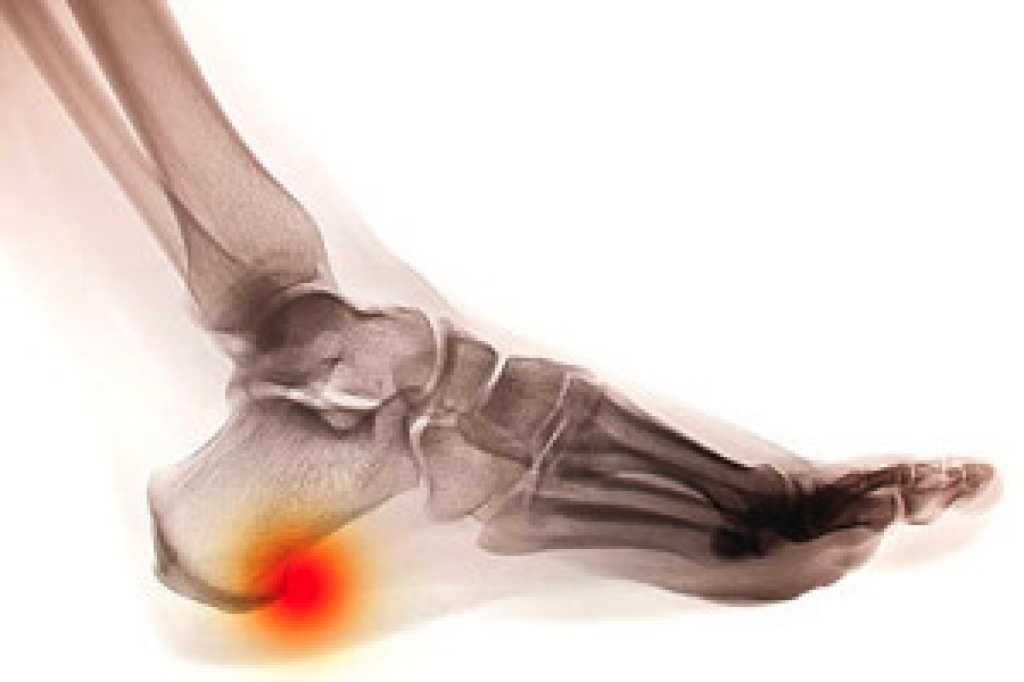

Treatment

To treat neuropathy in the foot, podiatrists will first diagnose the cause of the neuropathy. Figuring out the underlying cause of the neuropathy will allow the podiatrist to prescribe the best treatment, whether it be caused by diabetes, toxic substance exposure, infection, etc. If the nerve has not died, then it’s possible that sensation may be able to return to the foot.

Pain medication may be issued for pain. Electrical nerve stimulation can be used to stimulate nerves. If the neuropathy is caused from pressure on the nerves, then surgery may be necessary.